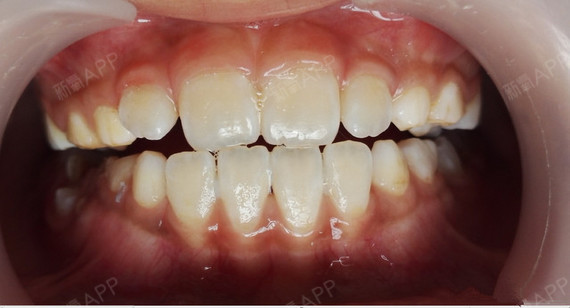

下牙套9个月后对比 门牙突 天生缺4颗牙 牙齿矫正